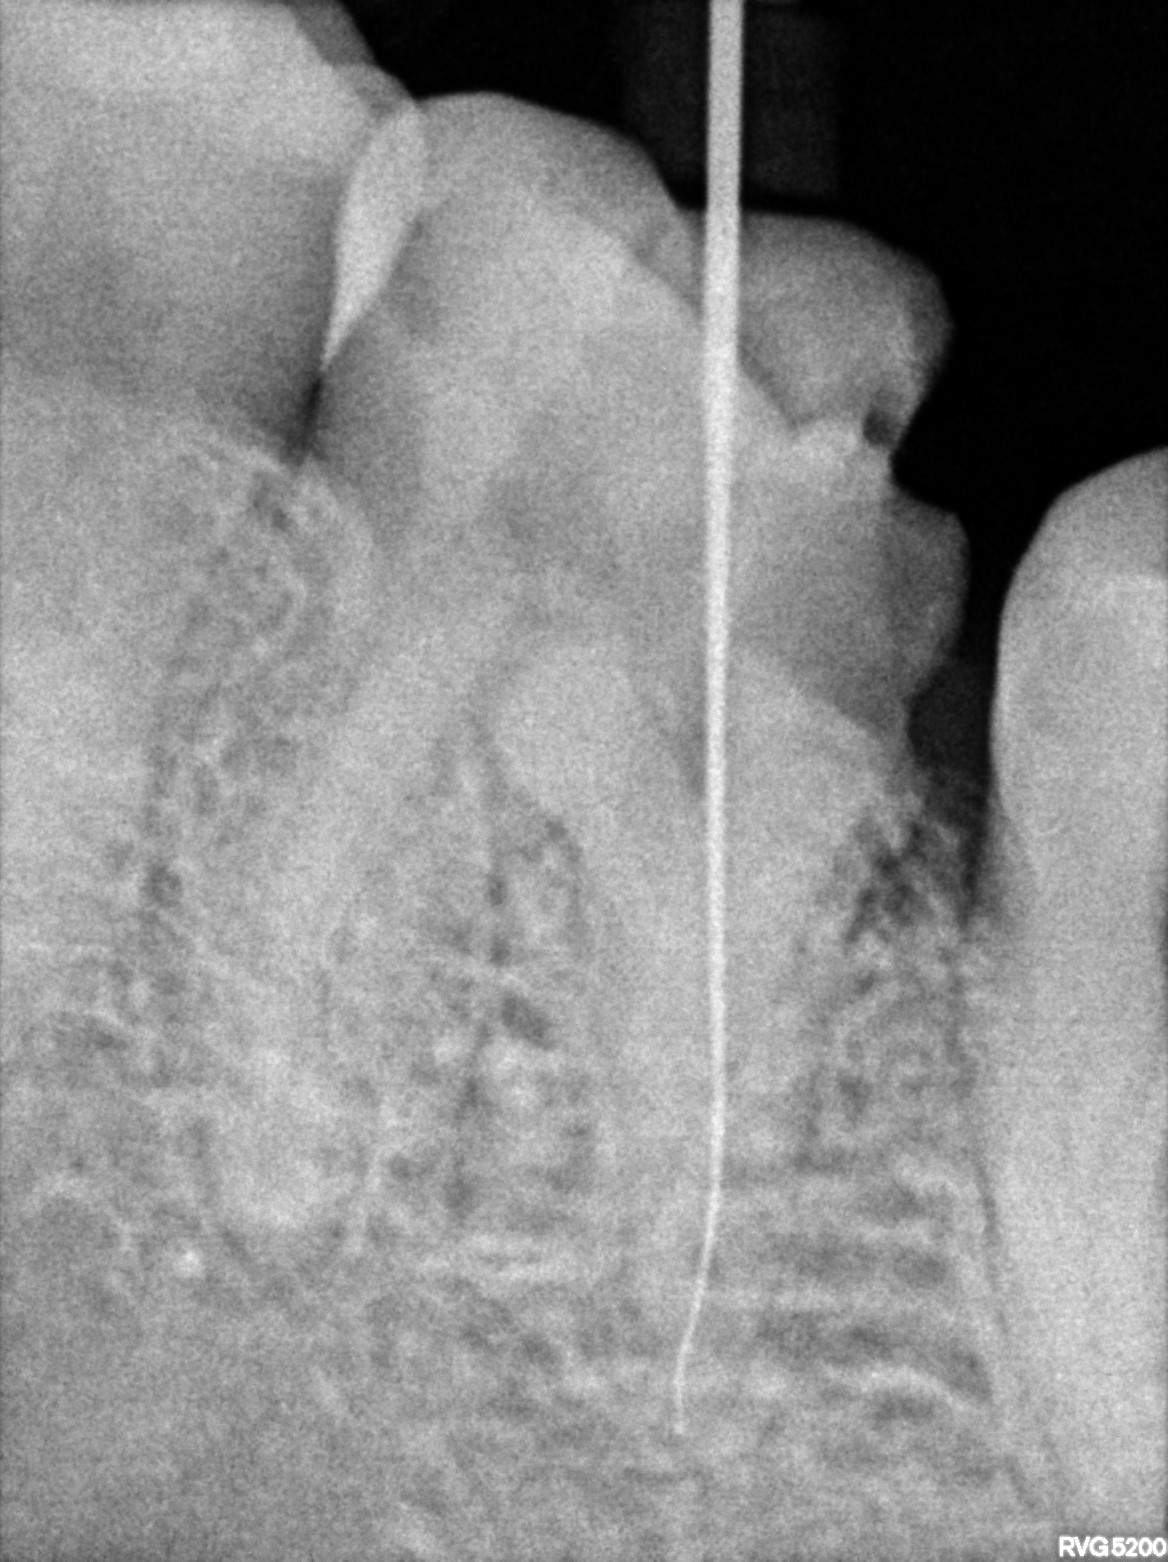

Dental Radiographs FHIR: DocumentReference · LOINC 24641-7

xray_1772642477_1.jpg

24641-7